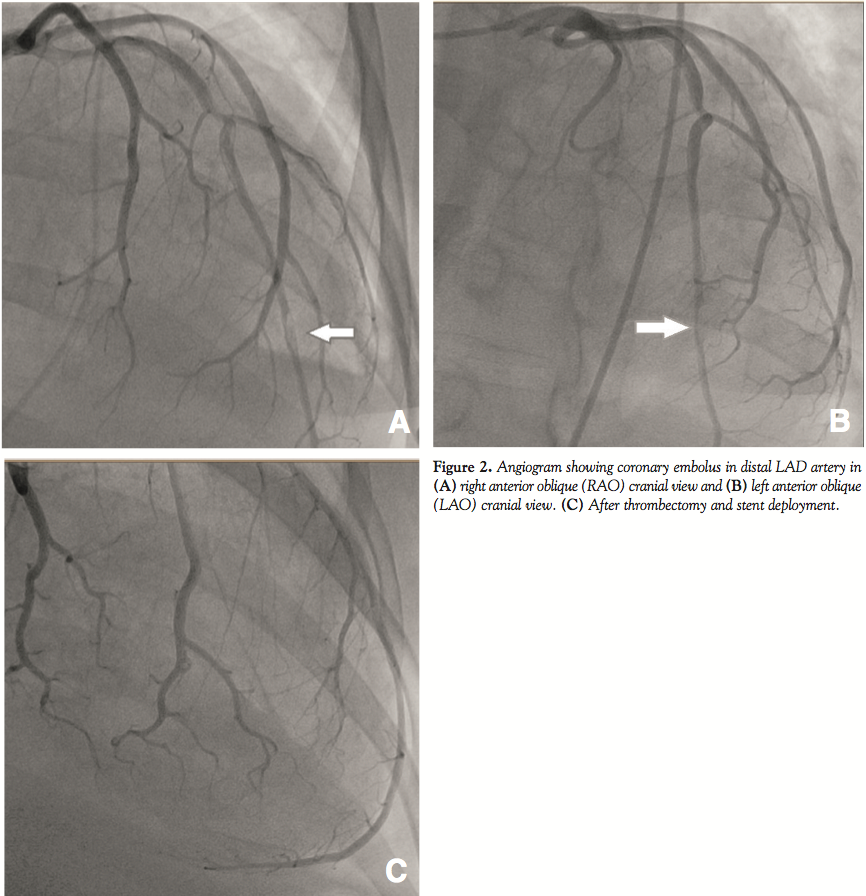

A 42-year-old African American woman presented with a past medical history significant for hypertension. She had an uncomplicated delivery 4 months prior following an uneventful first pregnancy. The patient presented to the emergency department with complaints of nausea, vomiting, and worsening shortness of breath for the past 24 hours. She denied any chest pain symptoms. The patient reported that similar episodes (also with no chest pain) occurred three times over the past few months. There was no family history of cardiomyopathy or premature coronary artery disease, nor had she any congenital heart disease. She was a non-smoker and denied use of illicit drugs. Physical examination revealed S3 and S4 heart sounds, bilateral lung-base crackles, and a body mass index of 36.6. An electrocardiogram demonstrated left bundle branch block with no previous documentation. Laboratory findings included troponin I and creatine kinase levels at 5.55 ng/ml and 60 U/L, respectively, CK-MB fraction <0.5 ng/ml, with a BNP level of 1440 pg/ml. Chest x-ray revealed marked cardiomegaly and pulmonary congestion. An echocardiogram (Figure 1) showed severe diffuse reduction in systolic function and global hypokinesia, an estimated ejection fraction of 15%, and multiple mobile left ventricular mural thrombi. In addition, the patient had an enlarged left ventricle (end-diastolic diameter, 7.4 cm), mildly enlarged left atrium, mild tricuspid regurgitation, and a small pericardial effusion without evidence of tamponade. The patient started becoming hypotensive and developed respiratory failure requiring intubation and ventilator support. She was taken emergently to the cath lab. Coronary angiography (Figure 2) showed an embolus causing an approximately 13 mm area of stenosis and 90% eccentric occlusion of the distal left anterior descending (LAD) artery; the other coronary arteries appeared normal.

Thrombectomy utilizing a Pronto™ catheter (Vascular Solutions, Inc.) of the distal LAD thrombus was performed, followed by balloon angioplasty at the site of the lesion; however, residual stenosis was still evident. A Multi-Link Mini Vision® bare-metal coronary stent (Abbott Vascular) was deployed. Flow improved to TIMI grade-3 following stent placement. A Swan-Ganz right heart catheter was inserted, and later an intra-aortic balloon pump was utilized due to persistent hypotension and cardiogenic shock requiring vasopressor support.